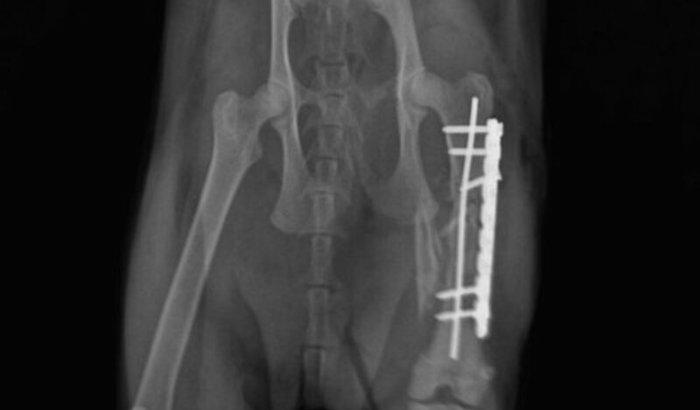

DIA ATUAL 24/01 - Maya fez a cirurgia e teve que colocar placas, pinos na sua perninha. Há riscos que podem levar a amputação mas Deus é maravilhoso e isso não irá acontecer. 🙌🏻